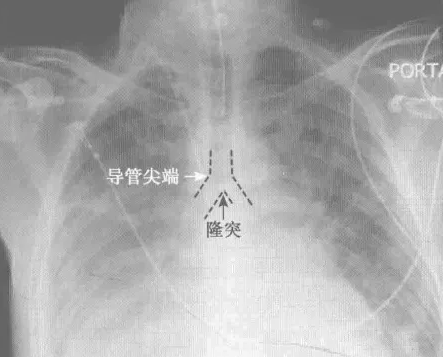

胸部X线能够确认CVC导管的位置,一般需要导管尖端在隆突水平(第四胸椎底)。X线应用在导管位置确认上有一定的限制,胸部CT可进一步明确其位置。